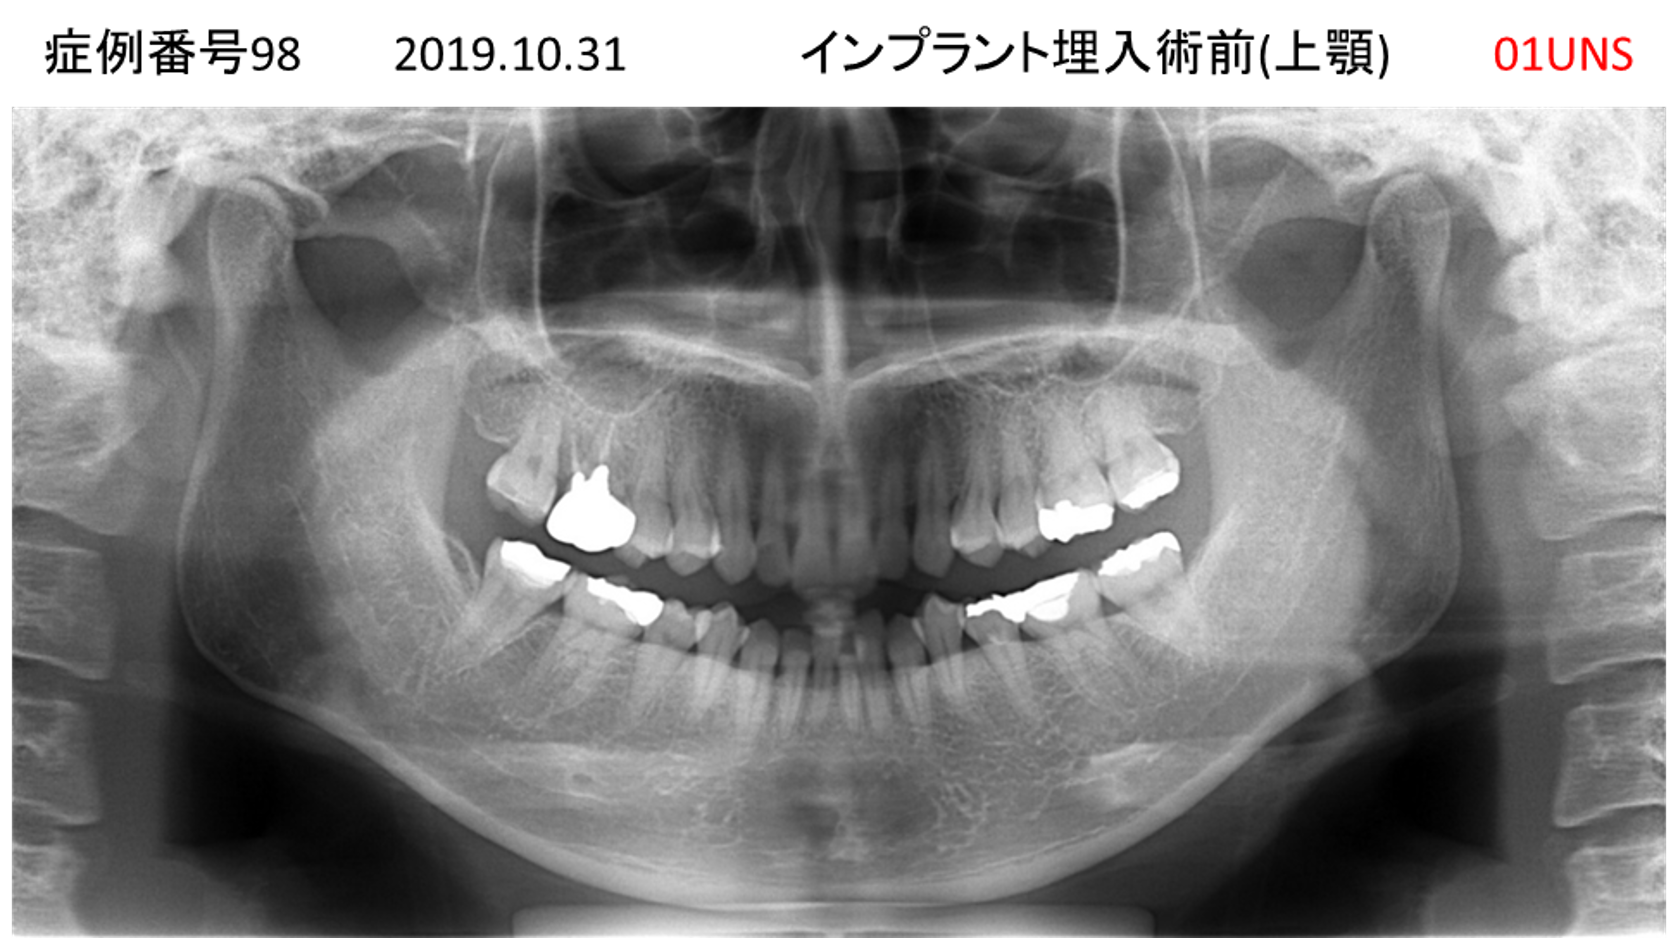

上の前歯が揺れてきてかめない患者様のインプラント症例

| 治療名称 |

インプラント |

| 治療費用 |

335万円+税 |

| 治療期間 |

4か月 |

| 患者さんの症状(主訴) |

上の前歯が揺れてきて噛めない |

| 治療内容 |

サイナスリフト 抜歯即時インプラント |

| 治療結果 |

ちゃんと噛めるようになった。不安がなくなった。見た目がとても良くなったのすごくうれしい。 |

| 治療の注意点(リスク/副作用) |

インプラントが壊れたら再治療が必要 |